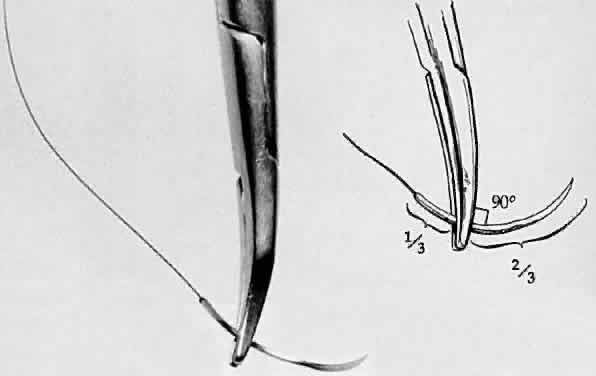

SUTURING TISSUE Three instruments are necessary to suture tissue properly. The first is

a tying platform to create multipurpose forceps (Fig. 27). It is a basic surgical principle that for any needle to pass through

general are very delicate. Ideally, the cross-section of the needle holder

should match the curvature of the needle, thus preventing needle

deformation when the needle is driven through tissue. Therefore, large, locking

needle holders may be used to grasp large needles, and fine

needle holders should be used for ultrasharp needles. With very fine, flat

jaws, there is little danger of needle damage when ultrasharp needles

are passed through tissue with minimal resistance. Ideally, the

needle holder should grasp the needle shaft one half to two thirds of

the way from the needle tip (Fig. 28). The needle is likely to flip if it is not seated at a right angle to

the needle holder. When the needle is properly seated in the needle holder, at

a 90-degree angle, the surgeon must flex the wrist to increase

mobility and pass radial sutures in all meridians. Simply dropping

the shoulder of the arm that is holding the needle holder increases the

surgeon's range of motion considerably. Lowering the magnification

during suturing enlarges the field and thus allows better manipulation

Fig. 28. A needle holder is shown grasping a surgical needle approximately two thirds

of the way from the head of the needle to the suture. The needle

is seated properly in the needle holder at a 90-degree angle. Fig. 28. A needle holder is shown grasping a surgical needle approximately two thirds

of the way from the head of the needle to the suture. The needle

is seated properly in the needle holder at a 90-degree angle.